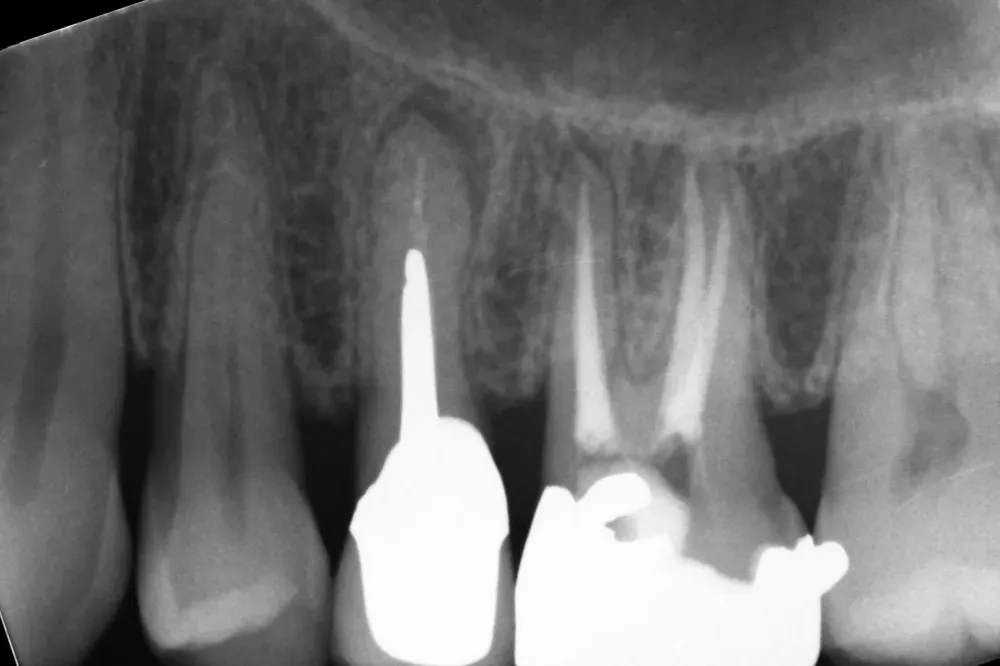

Seguono una serie di esami diagnostici specialistici come la radiografia panoramica e la TAC Cone Beam, fondamentali per valutare con precisione la quantità e qualità dell’osso disponibile. Spesso, sono necessari anche esami di laboratorio. Talvolta, è necessario effettuare anche altre visite specialistiche.

Gli esami strumentali permettono di simulare, ancora prima dell’intervento chirurgico, la posizione tridimensionale degli impianti per assicurarsi che non vadano a interferire con strutture anatomiche nobili come il nervo alveolare inferiore, il seno mascellare o le radici dei denti adiacenti che devono essere preservate.

Le immagini radiografiche che seguono testimoniano alcune delle tante soluzioni tecniche che ho utilizzato per le arcate a carico immediato nel corso della mia carriera. Ogni caso presenta sfide diverse e richiede un approccio personalizzato.